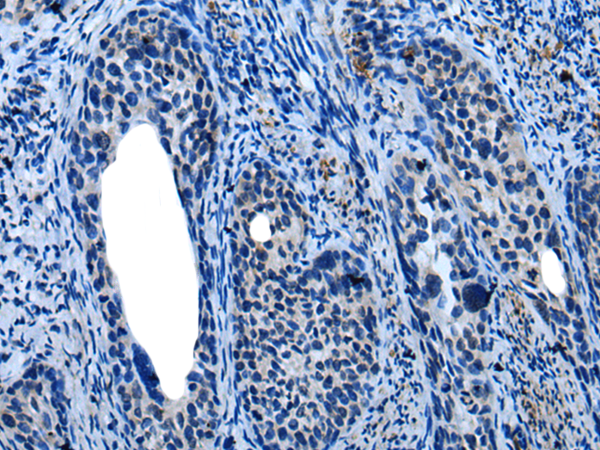

The image is immunohistochemistry of paraffin-embedded Human tonsil tissue using P12801(KLRK1 Antibody) at dilution 1/25. (Original magnification: ×200) |

The image is immunohistochemistry of paraffin-embedded Human cervical cancer tissue using P12801(KLRK1 Antibody) at dilution 1/25. (Original magnification: ×200) |